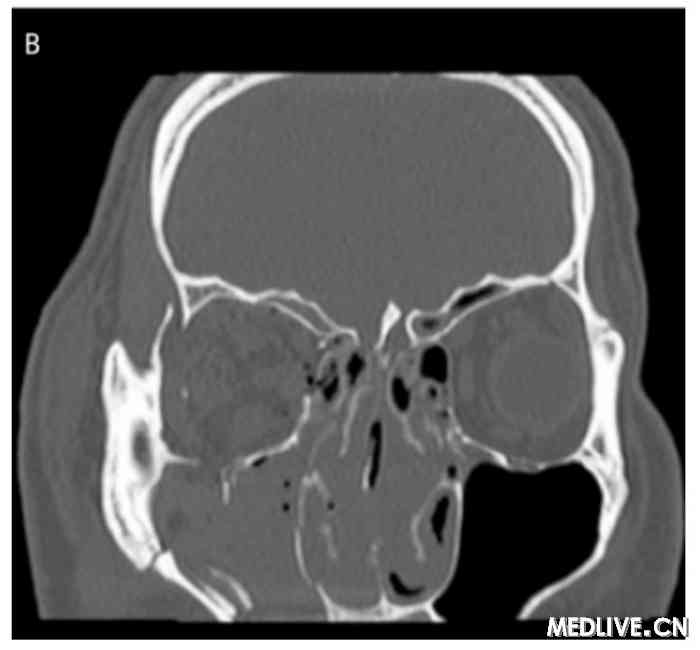

图2 双眶三维CT

B:右眼眶下壁骨折。